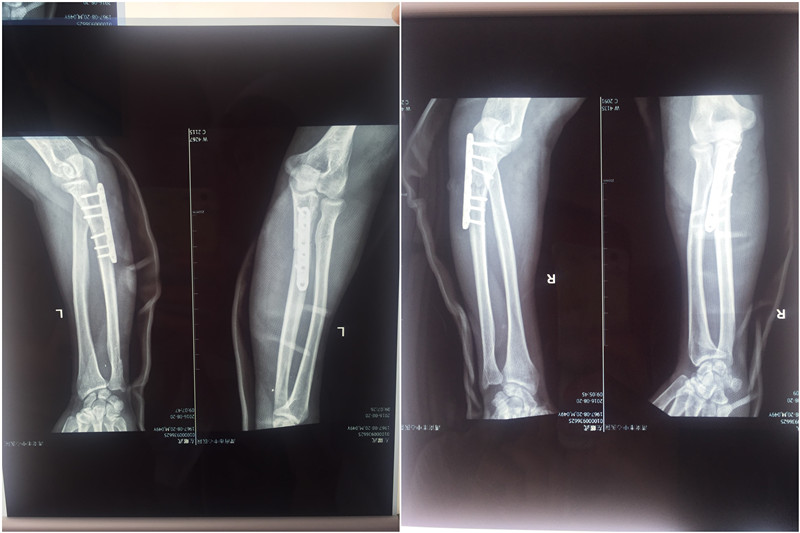

手术前

由于患者伤势严重、出血较多,家属非常着急,手术需立即进行。程福宏及郭张宏两位医师对此患者非常重视,迅速制定治疗方案,第一时间报告科室翁润民主任丶雷广宇副主任。患者由于出血多、多处骨折合并肌腱、肌肉、神经损伤需要立即手术修复。经过配血等术前准备,在麻醉手术科的协同下,历时7个小时手术,患者骨折得到复位固定,神经、肌腱等损伤得到修复,手术成功。经过骨一科医护人员20多天的精心治疗和护理,患者目前已进入后期康复阶段。患者及家属对骨一科医护人员精心治疗及护理非常满意,再三表示致谢。